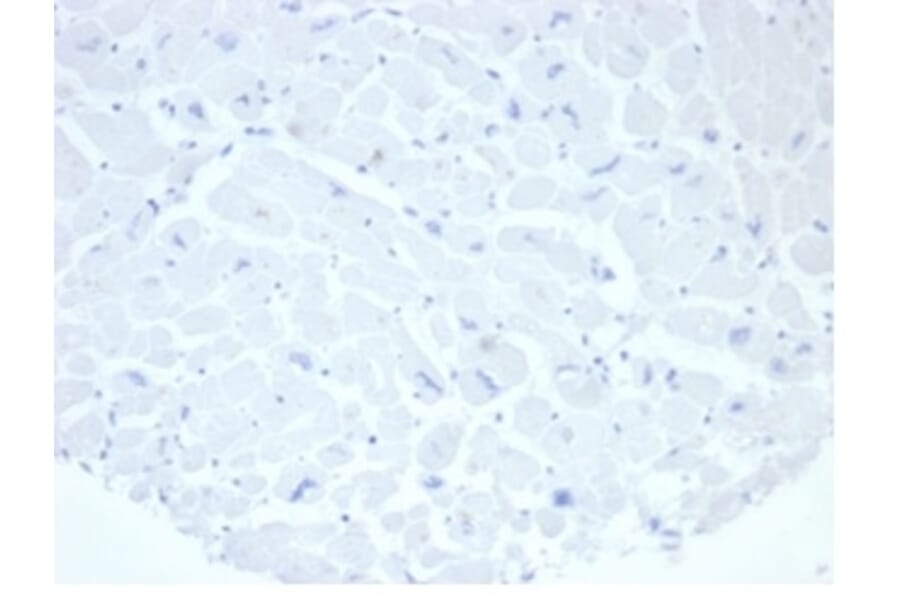

Anti-Placental Alkaline Phosphatase Antibody [rALP/870] (A277617)

Mouse monoclonal [rALP/870] antibody to Placental Alkaline Phosphatase for WB and IHC-P.

This antibody recognizes a 70kDa membrane-bound isozyme (Regan and Nagao type) of Placental Alkaline Phosphatase (PLAP) occurring in the placenta during the 3rd trimester of gestation. It is highly specific for PLAP and shows no cross-reaction with other isozymes of alkaline phosphatase. Anti-PLAP This antibody recognizes germ cell tumors and can discriminate between these and other neoplasms. Somatic neoplasms e.g. breast, gastrointestinal, prostatic, and urinary cancers may also immunoreact with antibodies to PLAP. Anti-PLAP positivity in conjunction with anti-keratin negativity favors seminoma over carcinoma. Germ cell tumors are usually anti-keratin positive, but they regularly fail to stain with anti-EMA, whereas most carcinomas stain with anti-EMA. Anti-PLAP has been useful in the diagnosis of gestational trophoblastic disease.

WB: 1-2 µg/ml, IHC-P: 1-2 µg/ml